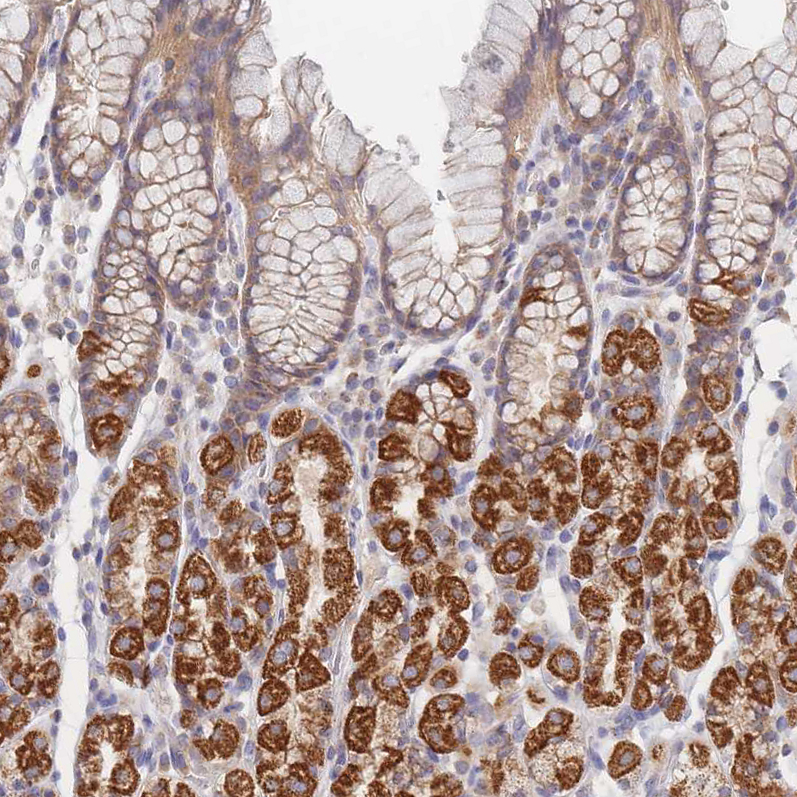

Immunohistochemical staining of human pancreas shows moderate cytoplasmic positivity in exocrine glandular cells.